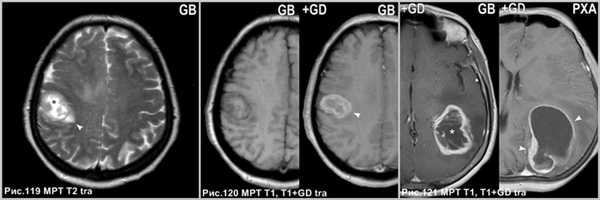

Глиобластома - злокачественная опухоль с быстрыми темпами роста, центральным некрозом, кольцевидным типом контрастирования, а так же выраженным перифокальным отёком.

Глиобластома представлена образованием с центральным некрозом (звёздочка на рис.119) и перифокальным отёком (головка стрелки на рис.119), интенсивно накапливающее контраст (головка стрелки на рис.120) по периферии с отсутствием в центре (звёздочка на рис.121) из-за некротического распада. ПКА накапливает контраст интенсивно и обозначает кисту с гладкими стенками (головки стрелок на рис.121).